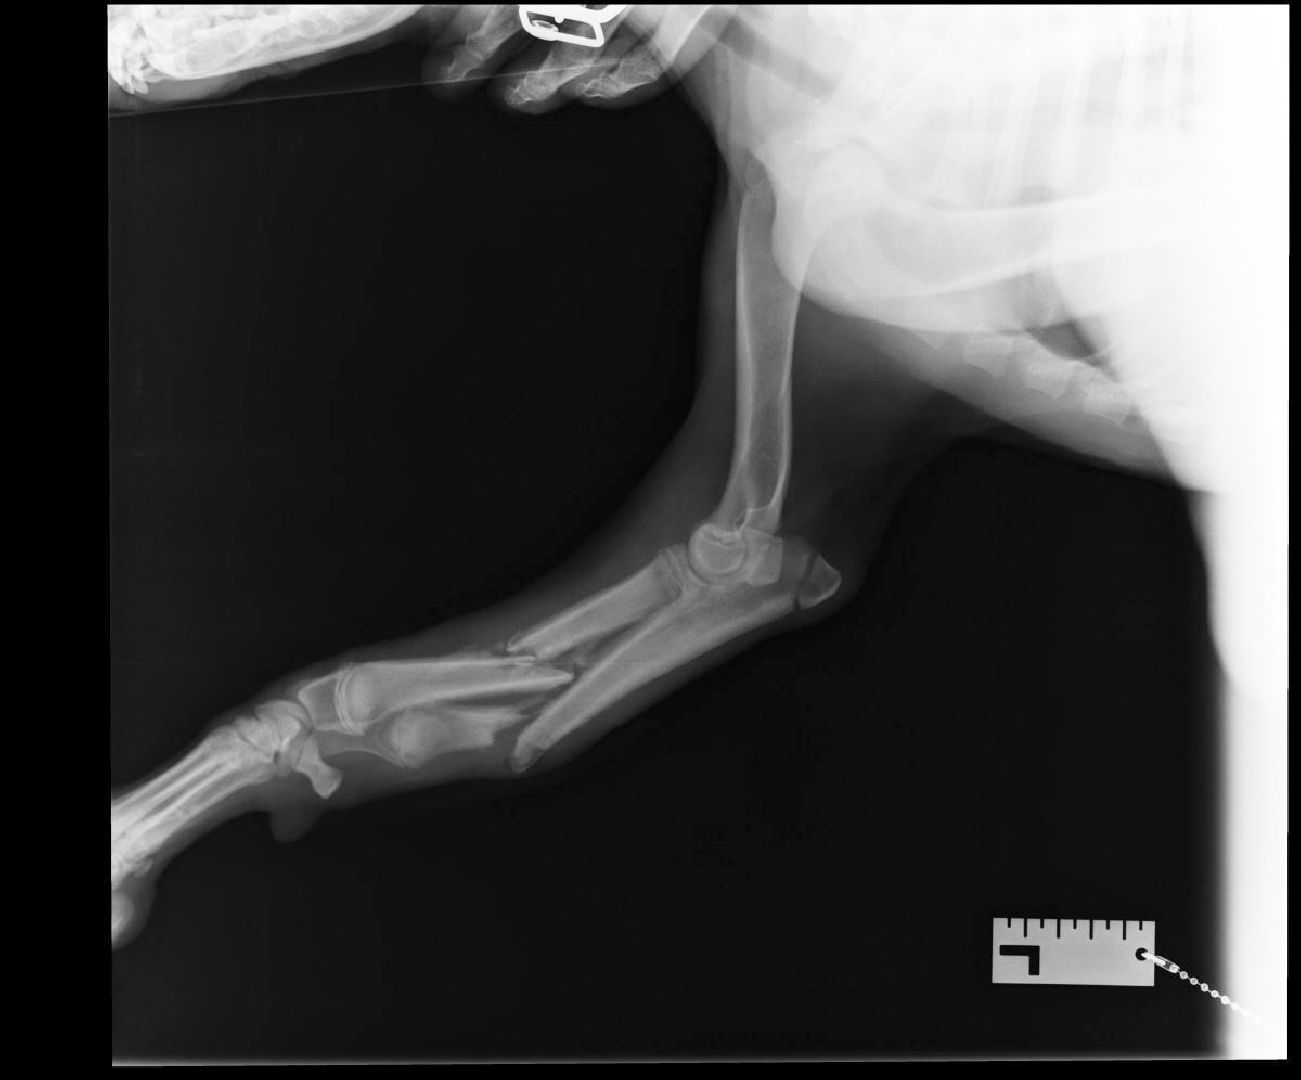

Неравнодушные жители обернули животное в одеяло, надели намордник и отвезли собаку в ближайшую клинику. На приеме у ветеринара были обнаружены множественные ушибы и раны, нанесенные твердым предметом, а также внутренние переломы по итогам рентгена.